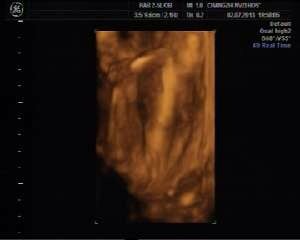

25周四维彩超看胎儿性别附照片 点击展开 匿名用户 2013-08-27 20:52 满意回答 恭喜发财,这是个男孩。 匿名用户 2013-08-28 10:38 宝宝知道提示您:回答为网友贡献,仅供参考。 相关问题 四维彩超看胎儿性别有没有出错的 25周胎儿四维彩超各项正常值是多少?做孕期糖尿病筛查,要做什么准备,什么时候做最好 怀孕25周了,还需要吃复合维生素(21)吗?做了个四维彩超,一切正常,还需要做其它什么检查呢?求回